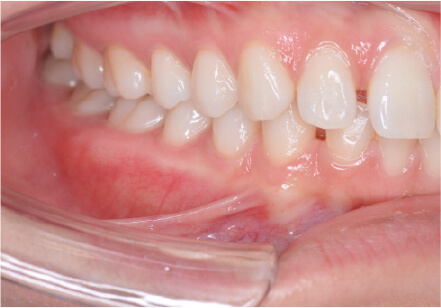

前歯前突の症例

8歳

男性

前歯が気になる

前突・叢生 アレルギー有

全額アライナー矯正 上下拡大装置使用

上下リンガルアーチ使用

痛み・歯根吸収・歯肉退縮・虫歯・後戻り

780,000円、1年8ヶ月